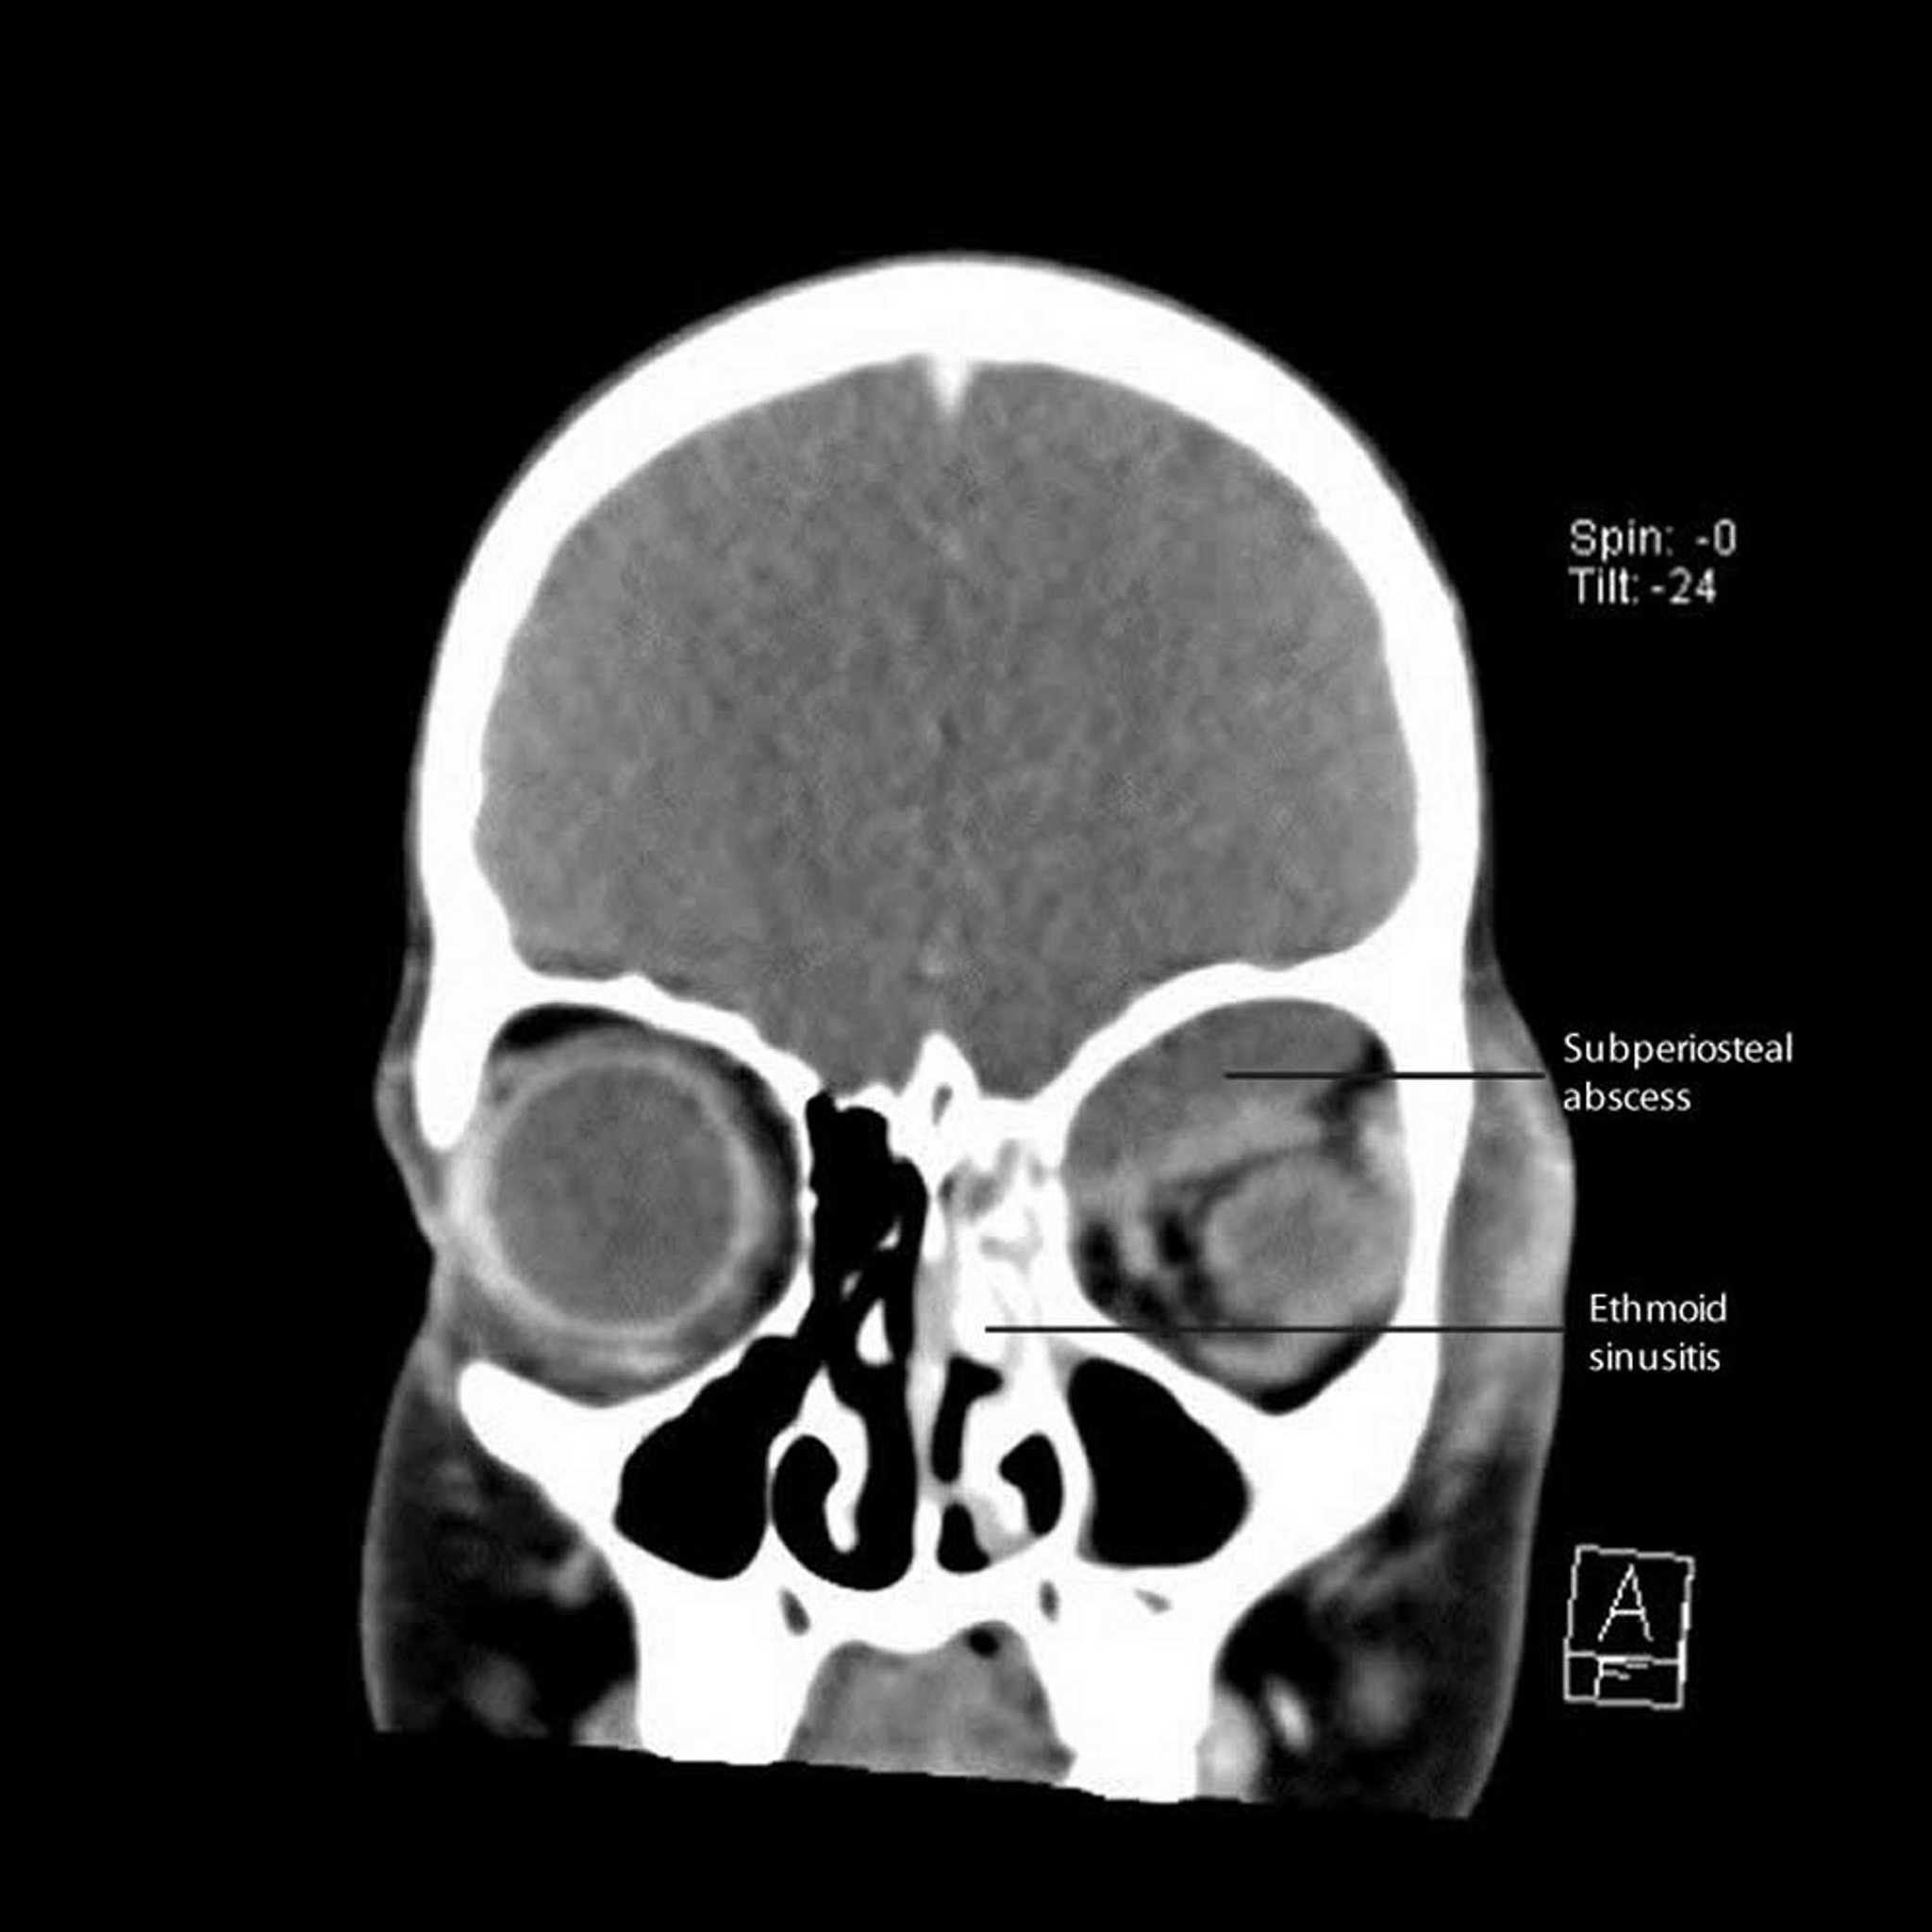

Sinusite etmoidal com abscesso subperiosteal

Essa TC mostra sinusite etmoidal esquerda com abscesso subperiosteal adjacente ao longo da parede medial e do teto da órbita.

CT courtesy of James Garrity, MD.